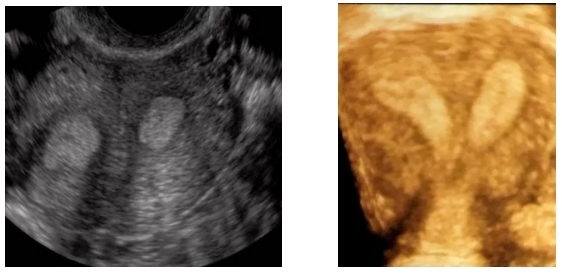

术中,宫腔镜冷刀技术精准切除子宫纵隔,将异常宫腔 “二居室” 修复为正常形态;腹腔镜手术则有效分离输卵管、卵巢周围粘连,全面修复生殖器官功能。手术全程微创,创伤小、恢复快,充分展现了团队的专业实力。

子宫畸形:纵膈子宫